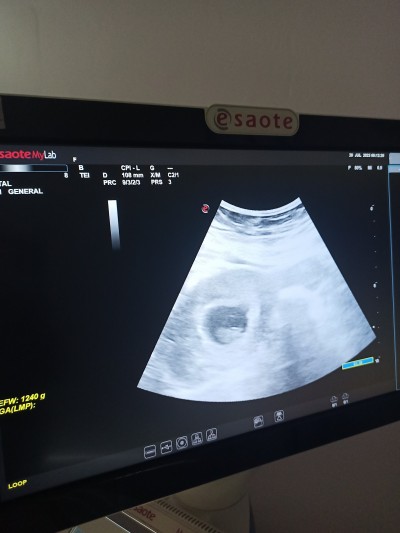

kizlar tahmin yapar mısınız devlete gidiyorum daha erken dedi kesesi böyle olup da cinsiyeti ne çıktı yakın zamanda

Gebelik haftası 12+4

Bende 13+5 teyim hala öğrenemedim ama kesesi böyle yuvarlak olan erkekmiş galiba öyle dediler banada haftaya doktora gidiyim öğrenirim.insallh bnmde kesemez böyle size yazarım

Bende yuvarlak kız fasulye gibi erkek diye biliyorum canım

Bnmki yuvarlak kız oldu kizlarinli yuvarlak

Kız kesesin benziyor yuvarlaksa kız fasulye gibi uzunsa erkek derler benimki de sen gibiydi kız çıktı hayırlı olsun simdiden

Valla benimde böyleydi kız dediler kız çıktı canım

Erkek canım seninki,kesin öğrenince geri dönüş yaparsın bak bbu benim kızımın kesesi

Benimde kız ve ultrason fotoğrafları böyle kesin kız ❤️